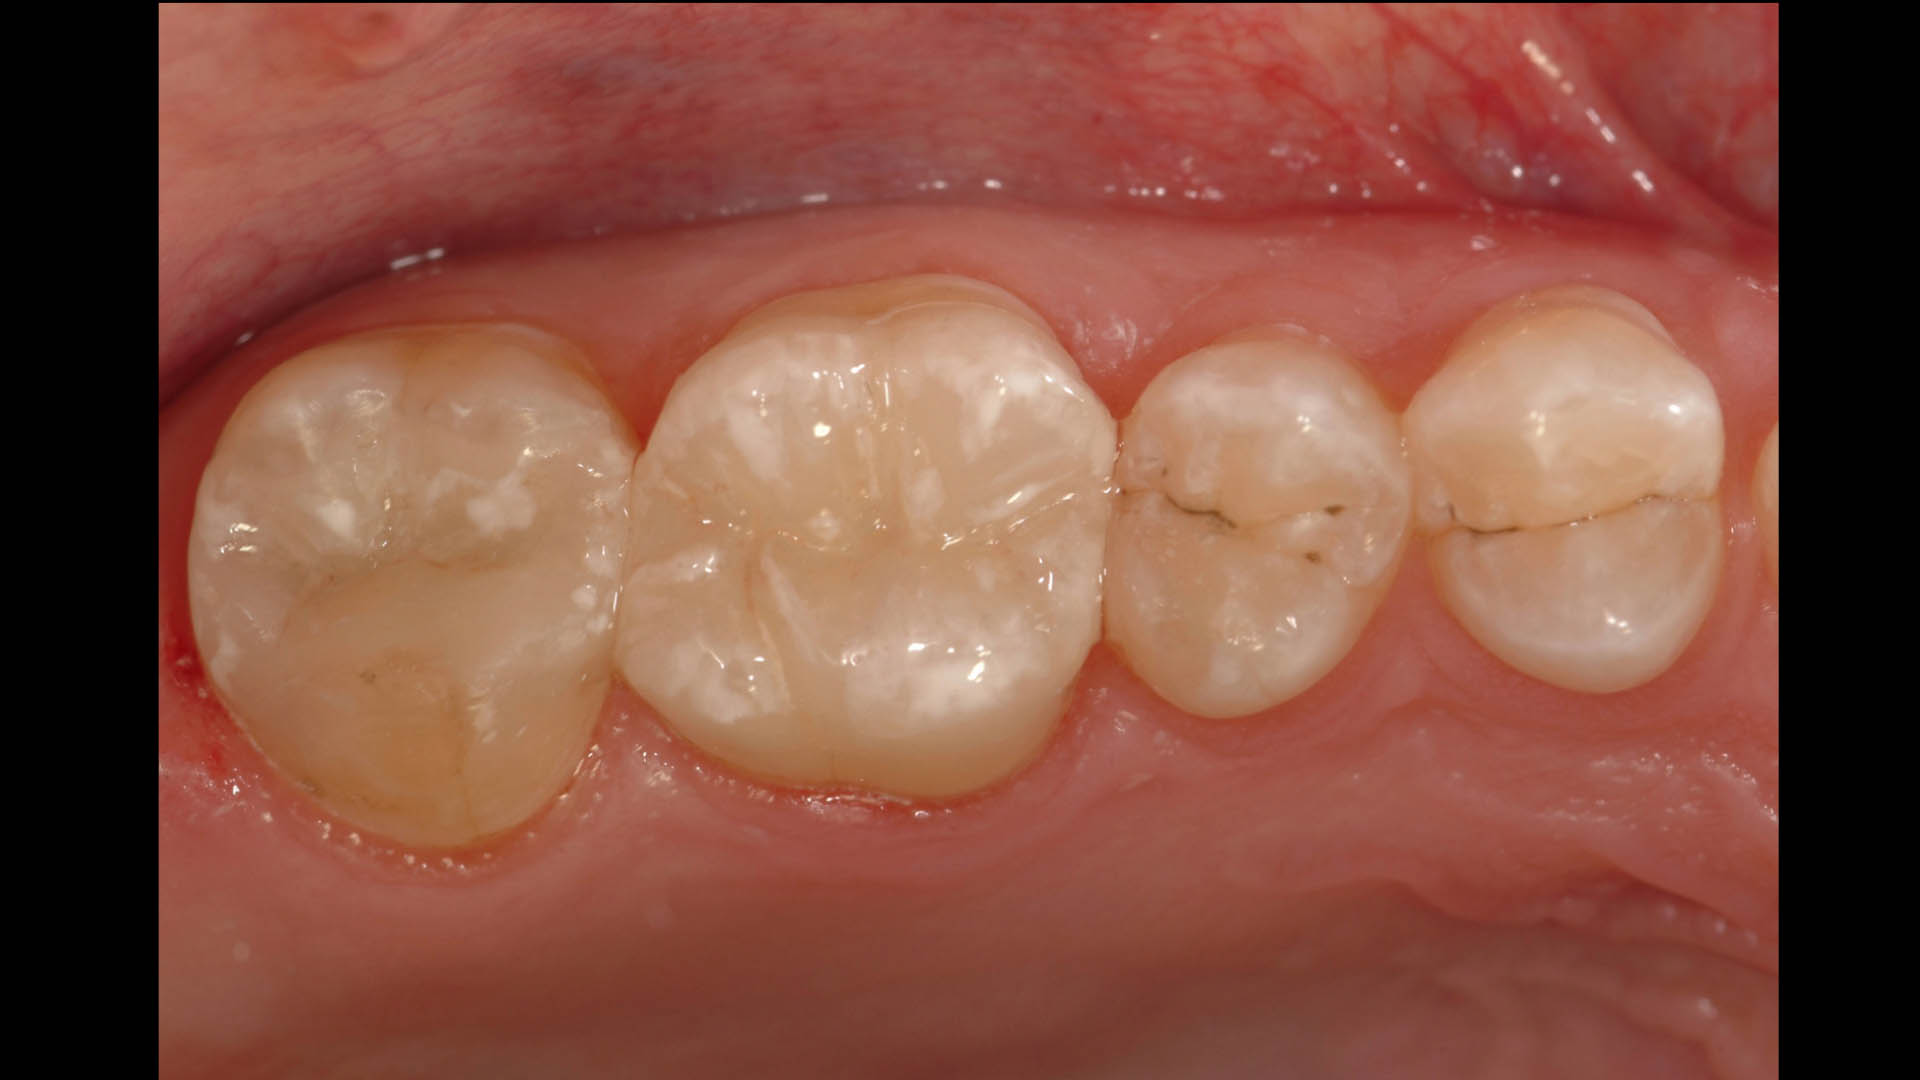

Take a glimpse into the magic of Coral Gables Dentistry through our before and after pictures. See firsthand the incredible smile makeover transformations that have brought confidence and joy to our patients.